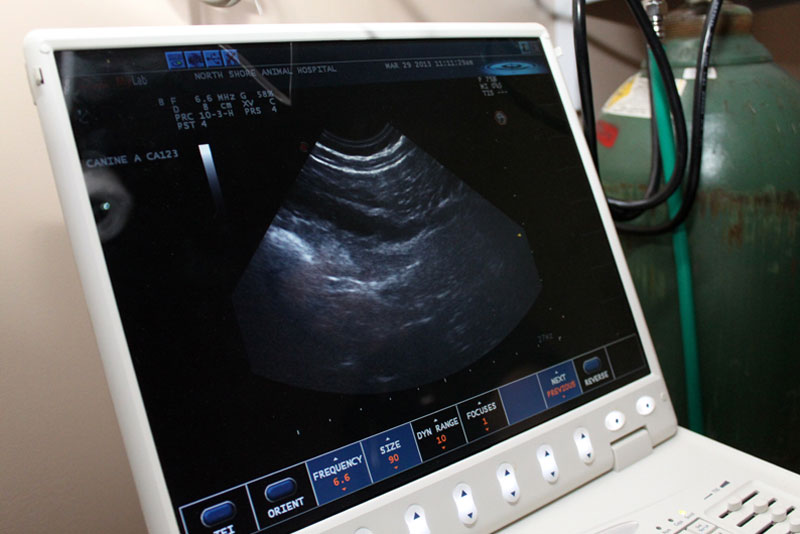

Ultrasound

Ultrasound is a non-invasive imaging tool that allows us to view your pet’s internal organs in real time. It is commonly used to evaluate abdominal structures such as the liver, kidneys, bladder, intestines, and spleen. In other situations, ultrasound may also be used to assess the heart or look for fluid within the chest or abdomen. This imaging tool provides detailed information about soft tissues and is often used alongside other diagnostics to help guide diagnosis and treatment planning.